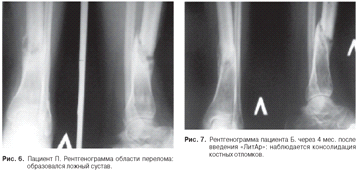

Пациент П., 43 лет. Косой перелом в диафизарной

части левой большеберцовой кости (рис. 5).

Пациенту П. был проведен чрескостный остеосинтез

по Илизарову. Иммобилизация в аппарате в течение трех месяцев. Из-за развития

воспаления в области спиц аппарат был снят. Иммобилизация гипсом. Развился

ложный сустав (рис. 6).

Через 9 месяцев после снятия аппарата Илизарова

был введен материал «ЛитАр» в область несращения (ложного сустава) инъекционно

под рентгенологическим контролем. Через 4 месяца наблюдалась консолидация

костных отломков

(рис. 7). Полная консолидация наступила через 6

месяцев.